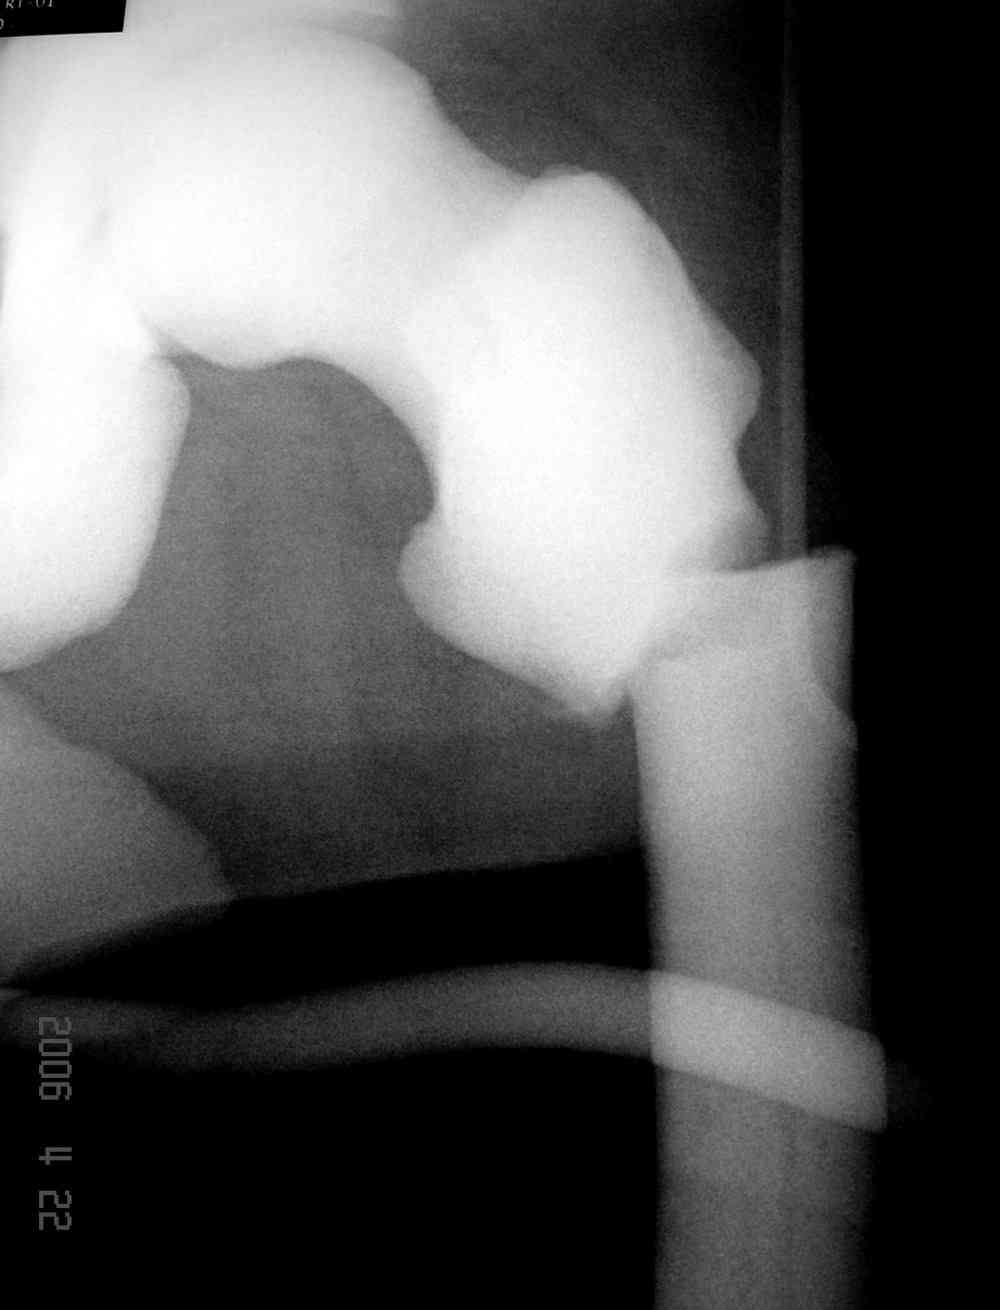

Здесь у меня дополнительные снимки с большим разрешением и в разных режимах, а то те дигитал снимки совсем очень блеклые, может, эти изображени изменят выбор тактики

После неудачной попытки скелетного вытяжения в первом мед.учреждении, после осмотра снимков и изучения истории, поставили диагноз “Остеопетроз” или мраморная болезнь, редкая наследственная костная паталогия, где имеется нарушение формации остеокластов.